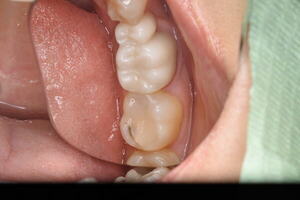

適合が悪いため、虫歯が再発 虫歯を取り除き治療終了